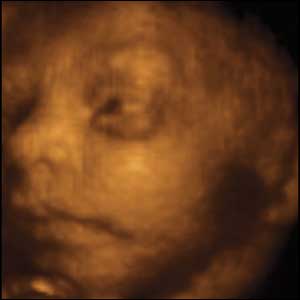

Part of the push to lower the abortion limit was the new ultrasound technology which could produce images like this one, taken at 24 weeks:

But other doctors disagree about lowering the legal limit for abortions. Retired obstetrician Wendy Savage said of the pictures:

“What we have seen are advancements in imaging. This may have raised emotions but they are not scientific evidence of the foetus developing any more rapidly.”